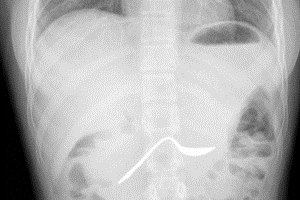

מוקד סקלרוטי הוא מעין גרעין של עצם צפופה זה יכול להיות גוש של עצם נוורמלית צפופה יותר הנקרא גם "אי עצם" וזה יכול גם להיות ביטוי של יצירת עצם מוגברת כתוצאה מגרוי מקומי כל שהוא. IUD= התקן תוך רחמי

שלום, חשד לנוזל פליאורלי אבל הצילום לא תמיד מאפיין בתורה מלאה את התמונה האמיתית ולעיתים כדאי לעשות סיטי להיות בטוחים.